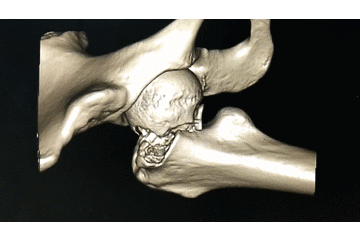

辅助检查:CT 检查提示右侧股骨颈骨皮质不连续,可见透亮骨折线及碎骨片影,断端错位、成角,周围软组织肿胀;右侧髋臼后下缘及左侧耻骨上支骨皮质不连续,断端未见明显错位;右侧髋臼后缘见类圆形稍低密度影,大小约 5*9 mm,边界清楚,边缘见硬化边;右侧髋关节在位,关节间隙未见明显变窄。

初步诊断:右股骨颈骨折(经颈型)